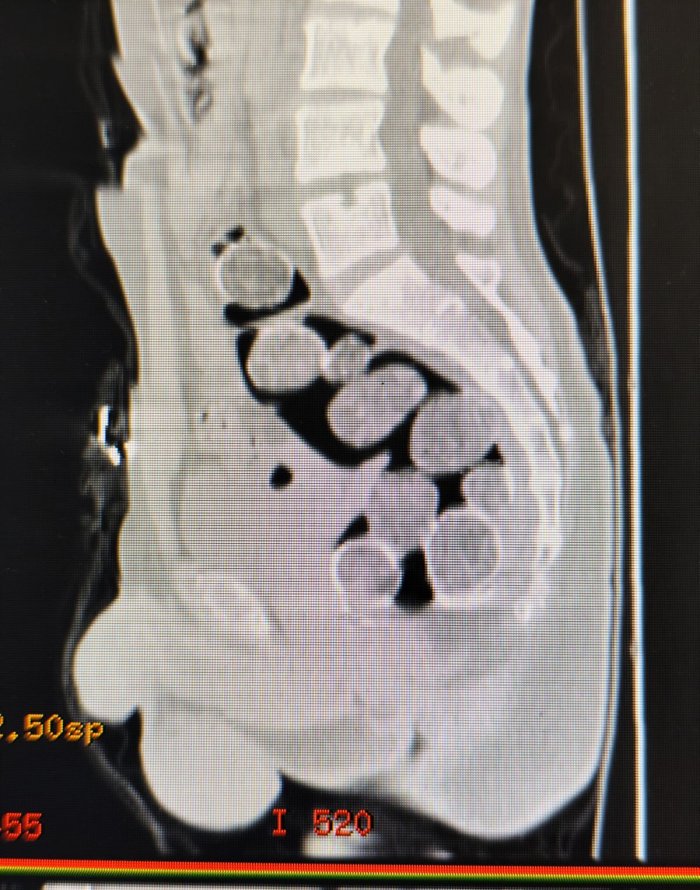

Samsun'da polisin takibi sonucu yakalanan 2 kişinin çekilen röntgen filminde mide ve bağırsaklarında 18 paket halinde toplam 500 gram metamfetamin ele geçirildi

Samsun'a yutarak uyuşturucu madde sokmak isteyen 2 kişi ile onları otogarda karşılayan şahıs, polisin operasyonu sonucu yakalandı. Samsun Cumhuriyet Başsavcılığı koordinesinde, uyuşturucu madde ticareti yapan şahıslara yönelik yapılan çalışmalarda İl Emniyet Müdürlüğü Narkotik Suçlarla Mücadele Şube Müdürlüğü ekipleri, Samsun'a uyuşturucu naklettiğinden şüphelenilen ve Samsun otogarına gelen A.A(36) ve H.T.'yi (44) takibe aldı. Şahısların binmiş olduğu araç İlkadım ilçesi Kıran Mahallesi'nde durduruldu. Araçta bulunan şahıslar ve araç üzerinde yapılan aramada herhangi bir uyuşturucu madde bulunamadı. Şahısların yanlarında valiz, çanta veya eşya bulunmaması ve A.A. ve H.T.'nin halsiz, tedirgin ve şüpheli davranışlar sergilemeleri üzerine yutmak suretiyle bağırsaklarında ve midelerinde uyuşturucu maddeyi getirebileceği değerlendirilerek, Samsun Eğitim ve Araştırma Hastanesine sevklerine karar verildi. Hastanede çekilen röntgen filminde, mide ve bağırsaklarında yabancı maddeler olduğu tespit edilen A.A. ve H.T. gözaltına alındı.

A.A. ve H.T.'nin mide ve bağırsaklarına yapılan tıbbi müdahale sonucunda, 18 paket halinde toplam 500 gram metamfetamin ele geçirildi. Şüpheli şahısların ikametlerinde yapılan aramada ise 1 adet ruhsatsız tabanca ve 99 adet fişek elde edildi. A.A. ve H.T.'nin yanı sıra onlara yardım ve yataklık ettiği tespit edilen R.K.(44) de polis ekiplerince gözaltına alındı.